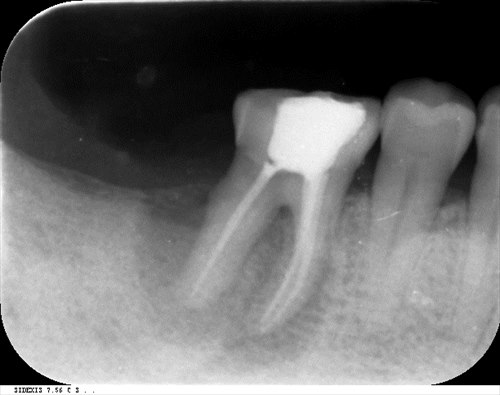

この症例も2回で根管治療は終了しました。終了時レントゲン